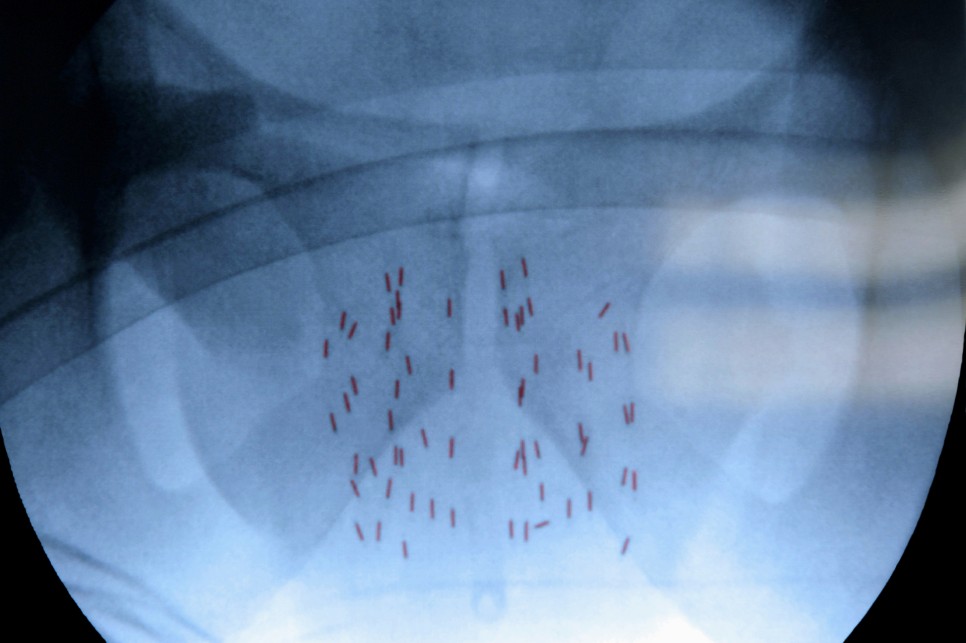

또 전체를 꺼내는 이유는 갑상선 전체를 제거하지 않으면 방사성 요오드 치료를 시행할 수 없기 때문입니다. 초기 암 이외에는 수술 후 4~8주 정도 방사성 요오드를 사용하여 남아있는 정상적인 갑상선과 잔여 갑상선암을 제거합니다.

방사성 요오드 치료를 필요로 하는 이유는 이후 재발빈도를 낮출 수 있고 재발이 발생해도 확인이 용이하기 때문입니다.

이후에도 주기적으로 갑상선암 전이재발의 유무를 확인하는 과정을 거치게 되며 이는 방사성 요오드를 통한 전신촬영/초음파검사/혈액검사를 통해 갑상선 글로불린을 측정하여 확인이 가능합니다.